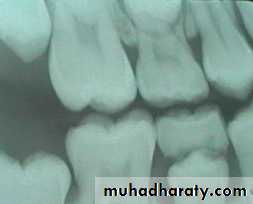

Morphological difference between primary and permanent teeth

The crowns of primary teeth :

are shorter

have a narrower occlusal table

have a more pronounced cervical constriction

have thinner enamel and dentin layers

• crowns of primary teeth :

• have broad flat contact areas between primary molars